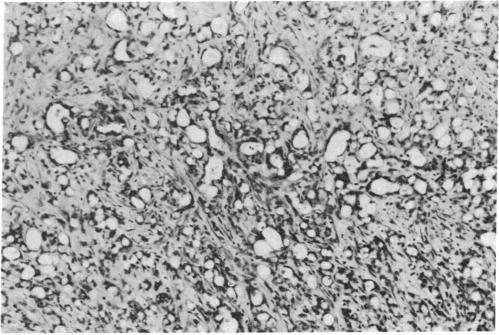

Female Syrian golden hamsters with N-nitrosobis(2-oxopropyl)amine (BOP)-induced ductal pancreatic cancers were treated with long-acting microcapsular preparations of the 6-D-tryptophan analog of luteinizing hormone-releasing hormone [( D-Trp6]LH-RH), releasing 25 micrograms/day; the somatostatin analog D-Phe-Cys-Tyr-D-Trp-Lys-Val-Cys-Trp-NH2 (RC-160), liberating 15 micrograms/day; and the combination of these two peptides. Therapy with analogs was initiated 24 weeks after initial administration of BOP. These treatments resulted in significantly better survival of all animals as compared to BOP controls; body weights of surviving peptide-treated animals were significantly higher than those of the BOP controls. All 15 BOP-control animals had pancreatic cancers. In the group treated with RC-160 four hamsters were free of tumors, whereas therapy with [D-Trp6]LH-RH resulted in seven tumor-free animals, and combination of RC-160 and [D-Trp6]LH-RH resulted in eight tumor-free animals from groups of 15. Only preblastomatous lesions were found in these animals. Average tumor weight of animals in all peptide-treated groups, sacrificed 60 days after beginning the peptide treatment, was significantly lower than that of BOP controls. No significant differences were seen between the various peptide-treated groups. Histologically, analog-treated tumors of hamsters showed striking regressive changes characteristic of programmed cell death (apoptosis). This apoptosis presumably resulted from hormonal effects on tumor cells from prolonged treatment with these analogs of hypothalamic hormones. Our present data confirm the beneficial effect of long-acting microcapsules of [D-Trp6]LH-RH and RC-160 on pancreatic carcinoma and suggest a mode of action for these peptides. The feasibility of applying this treatment with analogs of hypothalamic hormones to human pancreatic carcinoma can be envisioned from these studies.